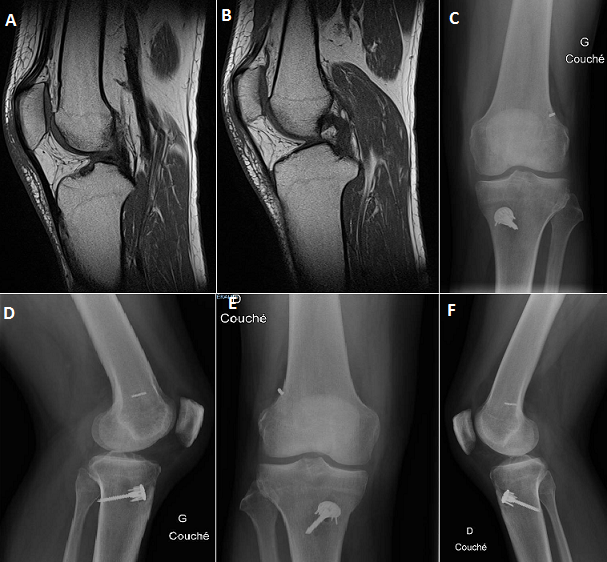

Un patient de 25 ans, victime d'un accident de ski (chute les 2 genoux en valgus flexion rotation externe) occasionnant chez lui une entorse grave des 2 genoux. Le patient a bénéficié d'une immobilisation par des genouillères plâtrées et revu à la consultation après 1 mois. Après 12 séances de rééducation on a noté une bonne évolution sur le plan de la douleur, en revanche le patient garde une instabilité avec sensation de dérobement à la marche et un signe de Trillat Lachman positif au niveau des 2 genoux, d'où l'intérêt de réaliser une IRM des genoux qui a confirmé une rupture bilatérale du ligament croisé antérieur (A, B). Nous avons réalisé une ligamentoplastie du LCA par la technique de DIDT au niveau des 2 genoux en un seul temps opératoire en commençant par le côté gauche. Les suites post-opératoires étaient simples, les radiographies de contrôles face et profil des 2 genoux ont montré un bon positionnement des implants (C, D) et une rééducation a été entreprise le lendemain de l'intervention. La reprise de l'activité sportive était sans problème au 6éme mois.